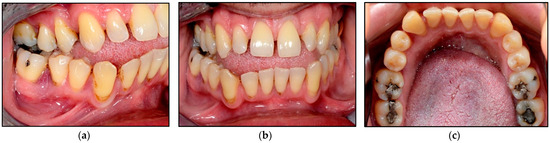

2.2.1. Clinical Examination

2.2.2. Investigations